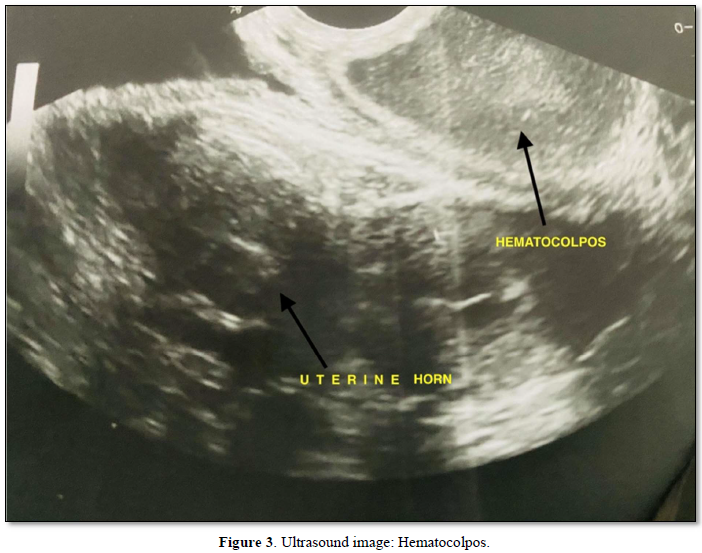

After that the patient had amenorrhea for 5 months accompanied by pain in the abdomen. Her general physical and local examination was unremarkable. She was investigated for amenorrhea. Her laboratory investigations and hormonal profile was within normal limits. Ultrasound showed a bicornuate uterus with hematometra in the right horn and left horn endometrial thickness of 11mm. 6X9cm hematocolpos (Figure 3) seen behind the urinary bladder. The right kidney is not visualized with the normal left kidney.